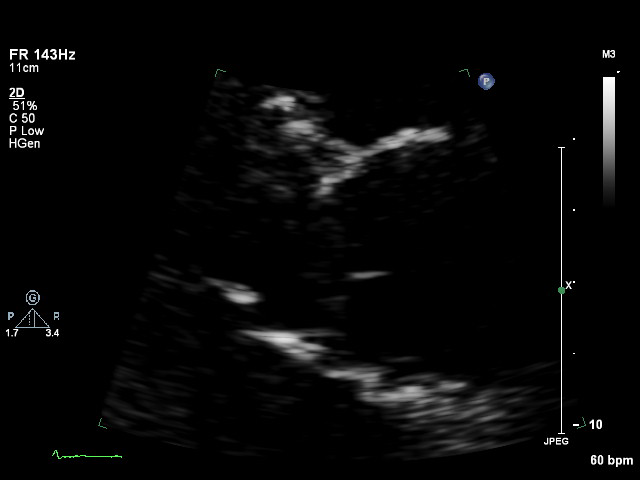

ImageView NameDescription

apex apex Any apical window whose depth is insufficient to reach the mitral ring